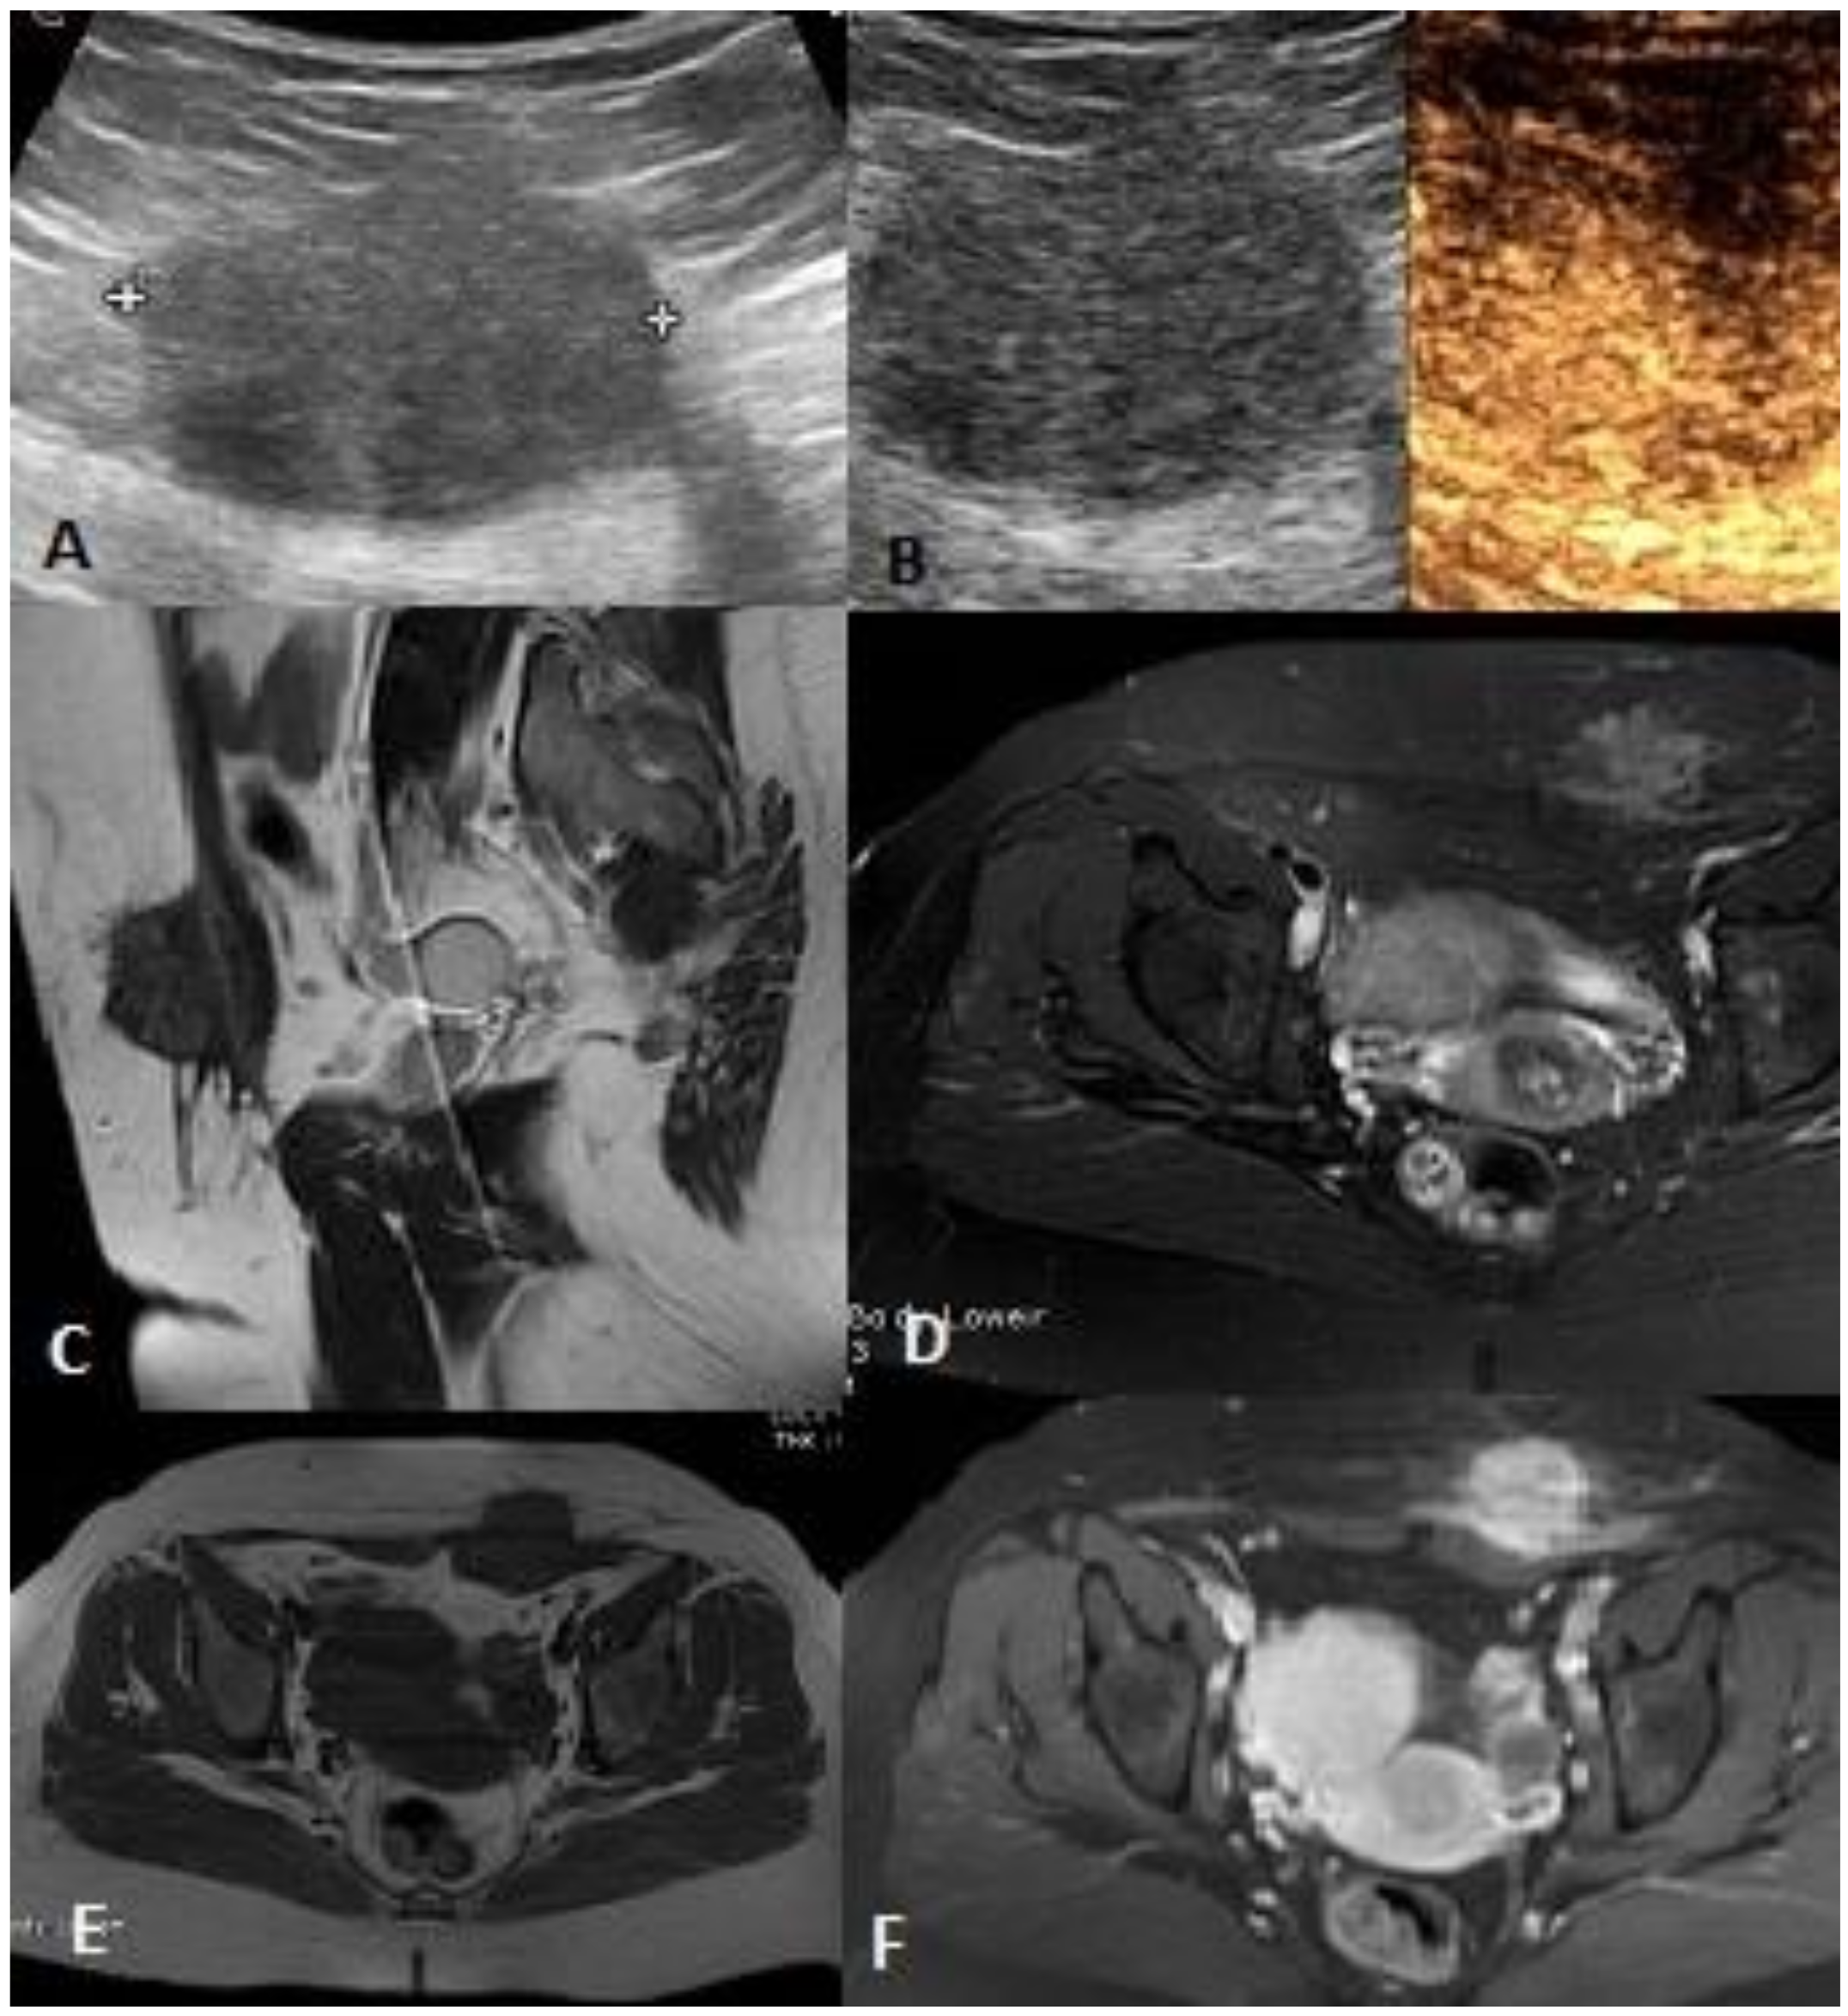

2.2.1. US and Power Doppler Sonography (PD)

2.2.2. CEUS

2.2.3. MRI